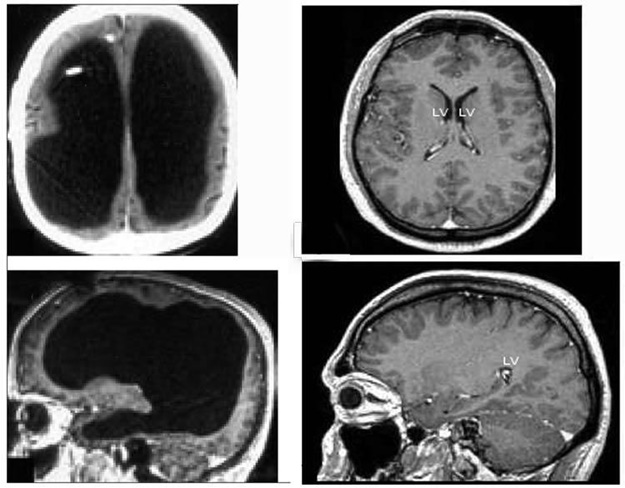

Webtekno sitesinde yer alan habere göre ülkesinde devlet memuru olarak çalışmaya devam eden adamın yaşadığı rahatsızlık ise halk arasında ‘beyinde su toplanması’ olarak bilinen hidrosefali. Beynin solunum merkezi gibi hayati bölgelerini içeren kısmının basıncın etkisiyle omuriliğe doğru kaymasıyla birlikte oluşan bu sorun, ani müdahale yapılmadığı taktirde maalesef ölümle sonuçlanıyor. Fransa’da yaşayan adam ise çocukken yaşadığı bu soruna zamanında müdahale edilmesinin ardından hayatta kalmayı başarmış.